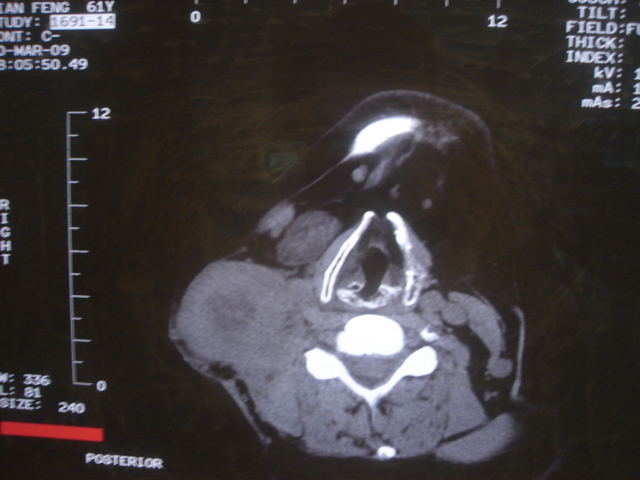

标题: CT18584:甲状腺Ca 喉转移?

患者 男 61  甲状腺ca术后7年 颈部淋巴结转移

声门下区表面不光整,增厚呈局限性突起,未见局部浸润.

考虑----颈部淋巴结转移,不排除---喉乳头状瘤可能.

颈部多个淋巴结增大,结合甲状腺ca术后7年病史考虑转移。

另声门区不规则突起,建议喉镜检查!

右侧颈部淋巴结转移,右声带乳头突起,乳头状瘤可能性大。

1)右侧颈部淋巴结转移瘤。2)右侧声带新生物,性质待定;建议喉镜检查(活检)。